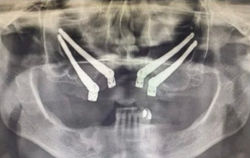

La chirurgia zigomatica rappresenta un'innovazione significativa nel campo dell'implantologia e della chirurgia maxillo-facciale. È una soluzione ideale per i pazienti con grave atrofia ossea mascellare che non possono essere trattati con impianti convenzionali. Gli impianti zigomatici, fissati direttamente all’osso zigomatico, offrono una base stabile per la riabilitazione protesica, evitando la necessità di interventi complessi come innesti ossei.

La chirurgia zigomatica ha dimostrato elevati tassi di successo grazie alla densità e alla qualità dell’osso zigomatico. Studi di letteratura, come quello di Chrcanovic et al. (2016), riportano tassi di sopravvivenza degli impianti superiori al 95% a lungo termine. La tecnica è particolarmente adatta per pazienti edentuli o con perdita ossea avanzata, offrendo predicibilità nei risultati e una rapida integrazione funzionale.

Grazie al posizionamento strategico degli impianti zigomatici, è possibile ottenere una riabilitazione estetica che ripristina armonia facciale e funzionalità masticatoria. La stabilità protesica consente ai pazienti di riacquistare fiducia e comfort estetico.